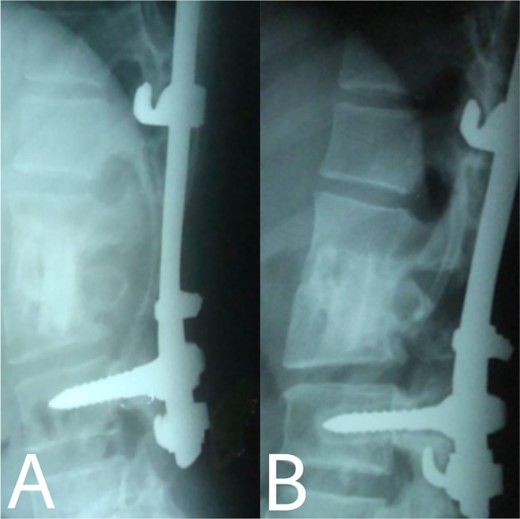

(A, B) Complete bony incorporation between the implanted fibular autograft and host vertebral body was noted on the lateral radiograph 1, and 14 years later.

Even though a spinal epidural abscess is a rare infectious situation, its incidence is increasing due to risk factors such as chronic illnesses, immunodeficiency states and drug abuse. MRI is an effective diagnostic test for spinal infection and to differentiate between TB and pyogenic spondylitis. It is difficult to determine the diagnosis when there are atypical manifestations of infectious spondylitis. However, in our case, MRI demonstrated the typical finding such as the compression of the spinal cord by the two vertebral endplates destruction, the epidural abscess, the disk signal and bone marrow abnormalities. Conservative therapy is the basis of spinal TB treatment. This approach is insufficient in some cases that require surgical interventions [4]. When indicated, delayed surgical management may lead to a bad prognosis [5]. As in our case, the paraparesis developed after 40 days of TB drug administration. These aspects necessitated surgical procedures to prevent further spinal cord compression [6]. Surgical techniques included posterior approach decompression, abscess resection, bone grafting and instrumentations. Spinal TB primarily impacts the anterior elements due to its blood supply profusion. Hence, the conventional approach has long been to use the anterior approach in spinal TB treatment [6, 7]. A prospective study has shown that the anterior approach has good results in a minimum period of a 3-year follow-up. Also, Ge et al [8]. reported a case of spinal TB involving the L1 vertebra with a massive paravertebral abscess. They used the anterior approach in the decompression and grafting with posterior instrumentations and their results were satisfactory. However, in recent years, the posterior approach proved its advantages, including its familiarity, enough space for an adequate debridement of the focal lesion, in addition to less surgical invasion. Both approaches lead to reduced operation duration and fewer rates of complications [9]. On the other hand, the anterior approach has its risks, such as abdominal visceral injury, and neural and vascular injuries. Moreover, spinal instability may occur [10]. As for grafting, we used an autogenous bone graft from the fibula for osseous loss, which may be considered a golden standard, because of its immune correspondence and osteoinductive capability [4]. There are considerations about inserting a bone graft in an infected site, like the surrounding tissue’s capability to provide the biological background for recovery. The presence of biomechanical stability enables biological reactions to enhance bone ingrowth [11]. Bansal et al. reported the fibular strut graft efficacy along with cancellous graft in an anterior approach and without instrumentations [12]. Singh et al. also showed the same results but without cancellous graft [7]. In our case, the bone graft was supported with the posterior (T10–L3) hooks combination and screws. Spinal cord decompression is the priority. Besides, the infected extracted tissues had to be replaced with another component for the spinal column stability. The X-ray showed a successful fusion post-operation. The medication was administered for 9 months to prevent the recurrence of the infection [13]. After treatment, the muscle strength became 5/5 up from the pre-operative 1/5. Within 14 years of follow-up, the X-ray demonstrated a good bone fusion and the patient’s status was good (Fig. 6). Minimally invasive spinal surgery (MISS) has been used increasingly over the past two decades [14]. MISS is performed using smaller incisions instead of traditional open approaches to accomplish spine surgical operations. MISS includes spinal endoscopy and robotics, which has improved the accuracy of instrumentation placement and virtual/augmented reality that has been very helpful for practicing surgical skills without patients. These techniques decreased the sedation requirements, blood loss and hospitalisation time [15]. In conclusion, early diagnosis of TB spondylitis with proper treatment and surgical intervention immediately after a neurological deficit can protect the patients from the chronic spinal deformity. The posterior approach was sufficient and effective in our case. However, the surgical procedure should be planned on a case-by-case basis. Fibular graft and instrumentations were effective, although they were inserted on an infected background.